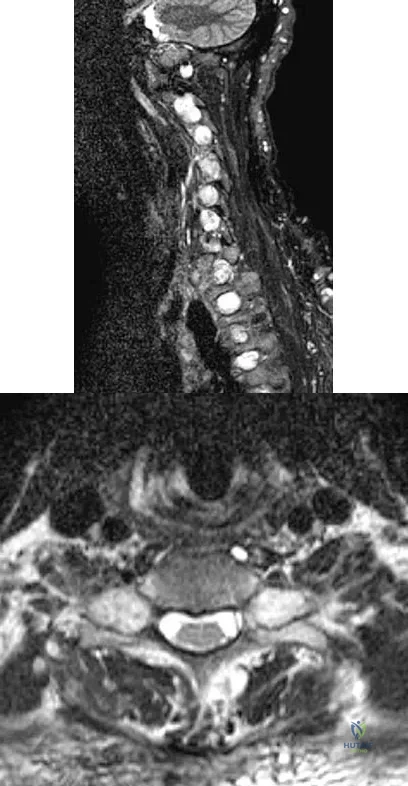

Question 96

Figures 3a and 3b show the MRI scans of a patient with neck pain. What is the most likely diagnosis?

Explanation